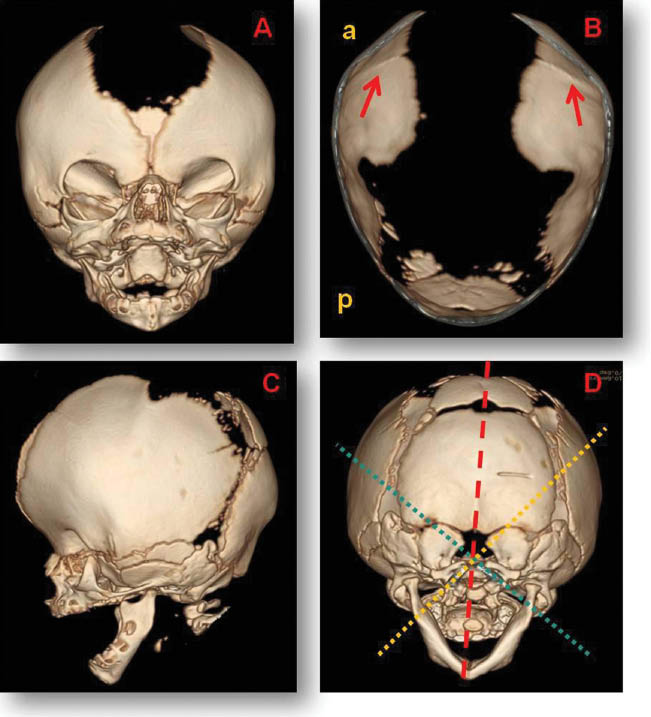

Vertebral and limbs X-ray, audiometry, echocardiography and abdominal echography were normal. In transfontanelar ultrasound we saw asymmetry because of left lateral ventricle enlargement. The scanner images showed cranial asymmetry with early closure of bilateral coronal and metopic sutures, a large bone defect of the sagittal suture, bilateral exotropia and deviated nasal septum (Figure 2). Radiologists made a 3D cranial scanner reconstruction to aid in defining the type of cranyosinotosis (Figure 3).

3D Cranial scanner images.

(A) Wide anterior fontanelle. (B) Bilateral coronal suture fusion and wide sagittal suture defect and posterior fontanelle [a: anterior, p: posterior]. (C) Turricephaly forehead. (D) Cranial asymmetry.